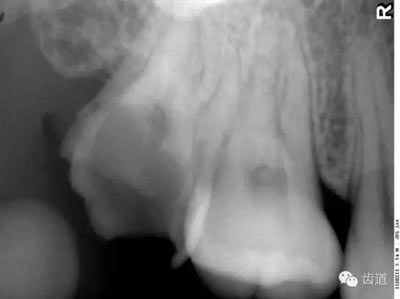

在投照上頜磨牙根尖片時(shí),經(jīng)??梢钥吹窖栏戏接幸幻芏鹊偷挠跋瘢瑸樯项M竇的一部分,邊緣環(huán)繞以密度高的線狀影像,為上頜竇壁致密骨層。有時(shí)可見(jiàn)上頜竇的分隔。

可在第一、二磨牙根尖上方或重疊在牙根上為近似三角形或半圓形密度高的影像。

常在上頜第二、三磨牙的牙冠區(qū)域有一較牙密度稍低由后伸向前方的三角形影像。

由升支前緣下部斜向前下方,為一密度高的帶狀影像。常重疊在第二、三磨牙牙冠處、頸部或根部,使牙髓室或根管不能清晰顯示